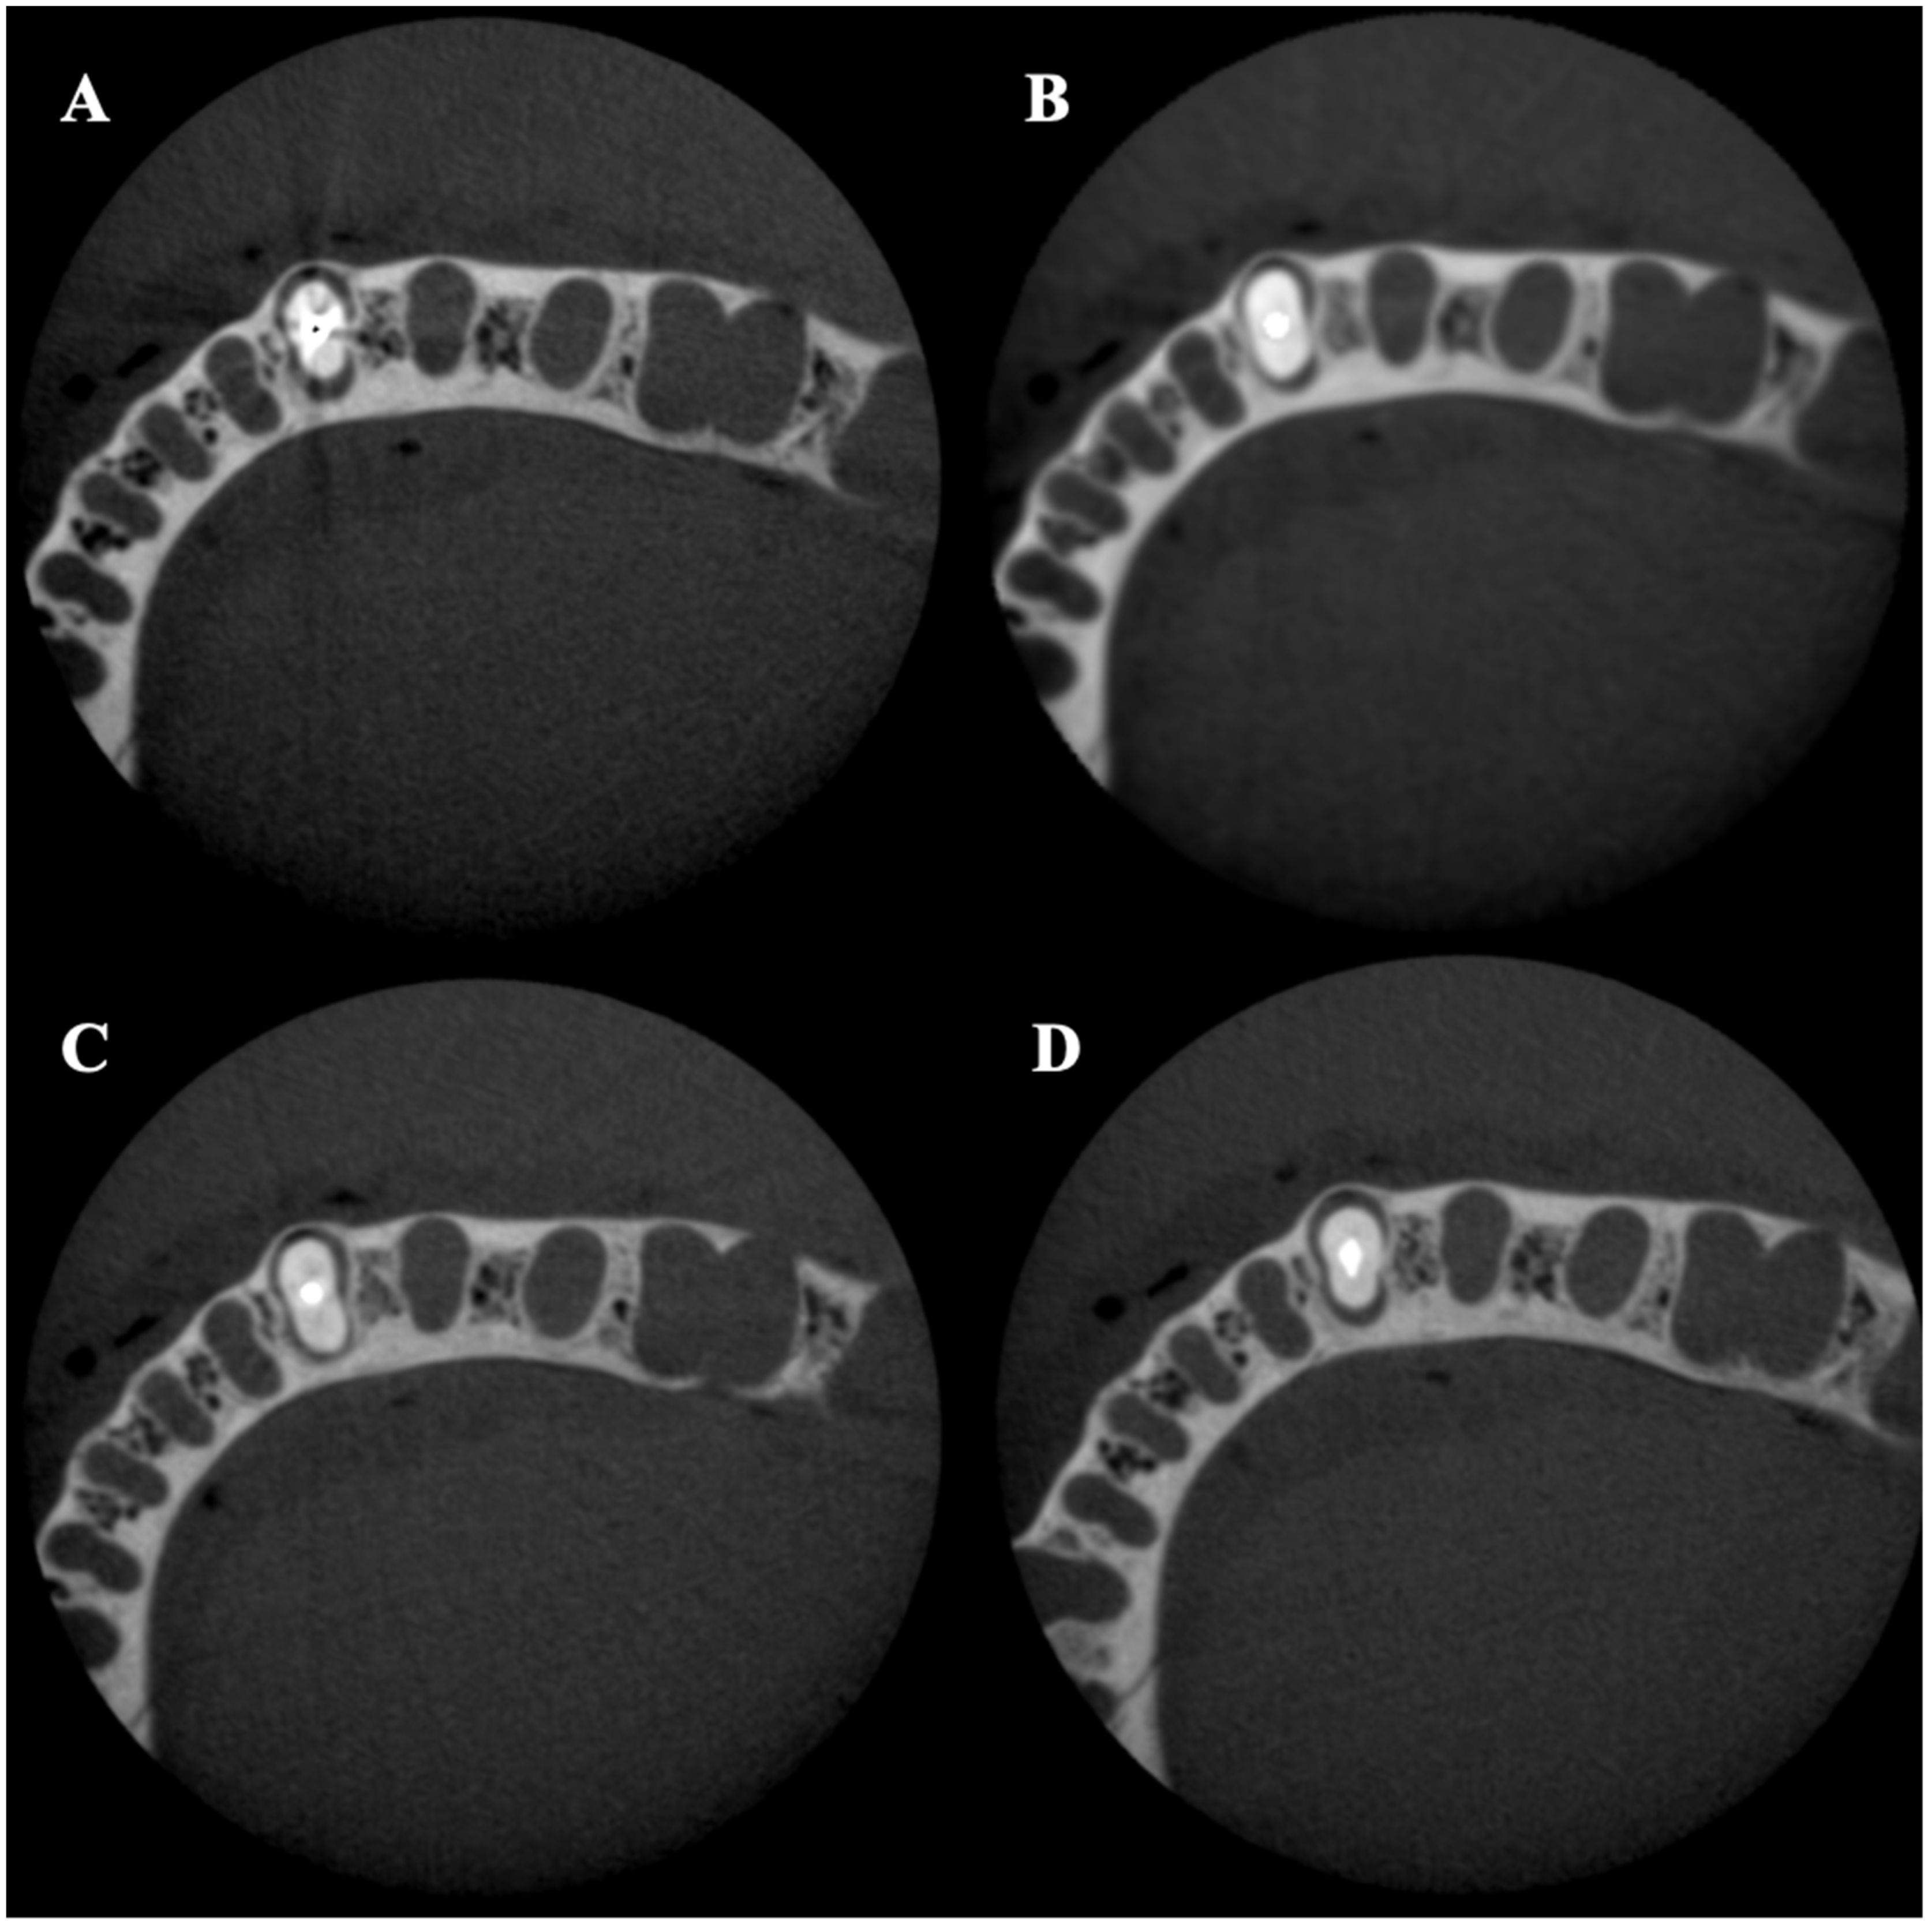

A total of 480 CBCT scans were acquired using multi-slice digital imaging in communications in medicine (DICOM) format with 0.16 mm thickness. For each volume, two slices were selected at 2 and 4 mm from the cementoenamel junction (CEJ), representing the cervical and middle root thirds (Figure 2).

Figure 2. Axial slices of middle thirds for each post material obtained with no MAR, 90 kVp, and 100 voxels: (A) gold-plated post; (B) titanium alloy post; (C) quartz fiber (Bisco DT Light) post; (D) glass Fiber (Rely X) post.